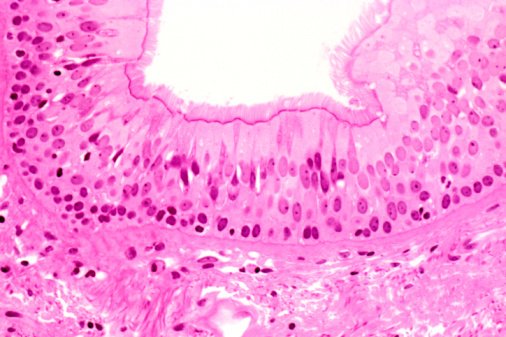

Describe the components seen on bronchi histology

Primary to tertiary bronchi

See respiratory epithelium: pseudostratidied columnar epithelium

underneath is Lamina Propria

under is smoot muslce with mast cells (issues d/t hitsamines)

As we go from conduction to respiratory system, what happens to epithelium?

Epithelium decreases